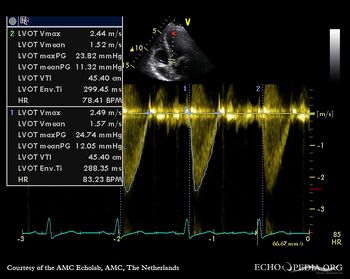

A3CH with Color Doppler: high velocity flow in LVOT Continuous-wave Doppler signal of flow in LVOT